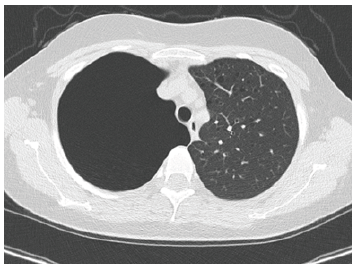

After ECG (normal sinus rhythm) and routine biochemical profiles (within normal limits) was subjected before to chest X-ray (large right-sided pneumothorax) and then to CT-scan to investigate secondary causes of pneumothorax which showed innumerable thin-walled cysts throughout both lungs (Figures 1,2) and angiomyolipoma in the left kidney.

Figure 2: Ct of the chest showing multiple thick walled cysts located throughout both lung parenchyma.